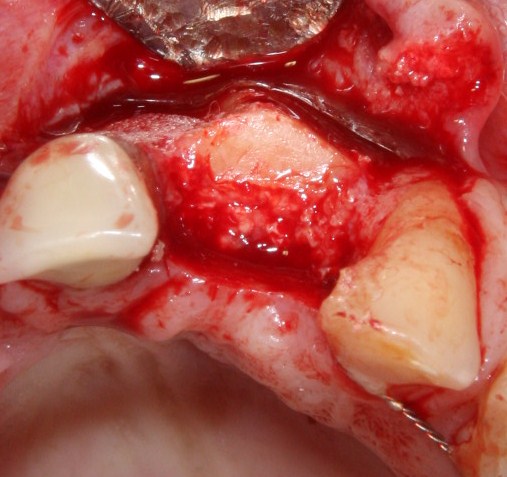

Давайте внимательно посмотрим на состояние лунок центральных резцов после удаления:

Приемлемый фенотип (сочетание толщины и ширины участка жевательной десны) — это, конечно, приятно. Но гораздо важнее сосредоточиться на рисках, их на этот момент два:

— травматическое повреждение слизистой, вызванное удаление зубов связано с тем, что при хроническом воспалении слизистая оболочка теряет эластичность, поэтому легко рвётся. Такая ситуация создаёт серьёзную угрозу эстетическому результату лечения, в зависимости от того, насколько быстро десна придёт в норму.

— как и предполагалось после КЛКТ, утрата костной стенки привела к тому, что десна провалилась в просвет лунки левого центрального резца. Это еще больше усугубляет клиническую ситуацию.

Для нас это не было неожиданностью. Зная закономерности изменений тканей при хроническом  воспалении и данные КЛКТ, мы можем довольно точно предсказывать развитие клинической ситуации и соответственно к ней подготовиться. Именно поэтому, помимо обычной немедленной имплантации, мы запланировали аугментацию лунки с помощью биоматериалов и метода трансплантации лоскута (см. предварительные планы лечения).